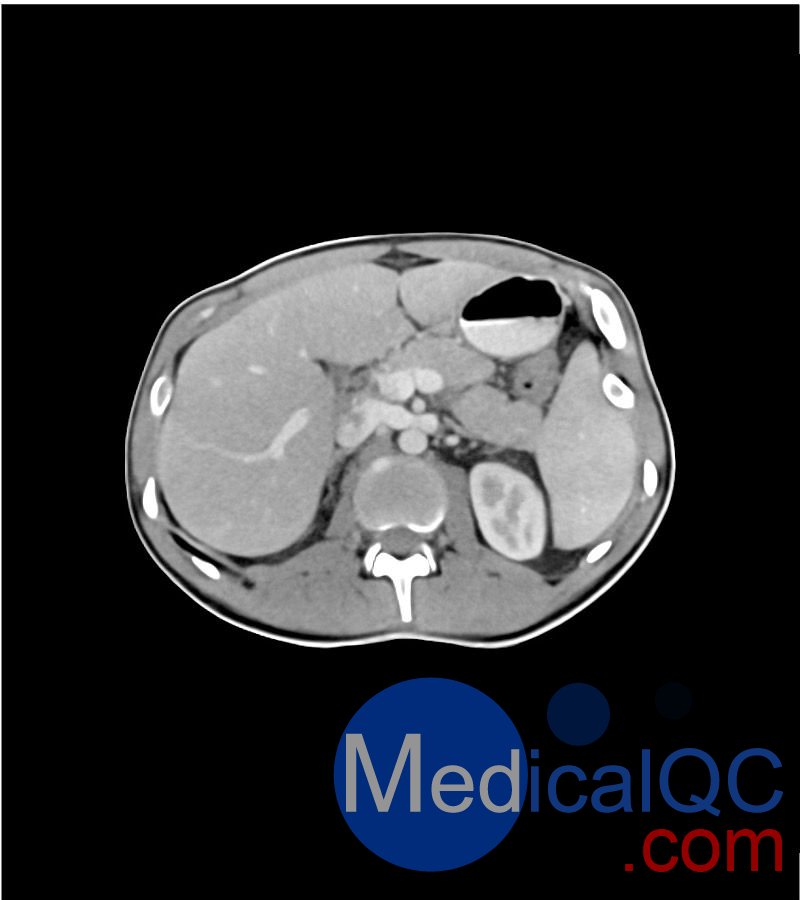

WEK-5501男性腹部模体,WEK-5501男性骨盘模体成像效果图:

WEK-5501男性腹部模体,WEK-5501男性骨盘模体可模拟门静脉期的腹部和盆腔增强扫描效果,扫描范围覆盖第一腰椎至会阴区域。

该体模右侧设有髂淋巴结肿块(模拟病灶)。

WEK-5501男性腹部模体,WEK-5501男性骨盘模体可用于计算机断层扫描(CT,含锥形束计算机断层扫描 CBCT),以评估和优化成像性能及后处理应用(包括人工智能辅助应用),同时也适用于相关培训场景。

WEK-5501男性腹部模体,WEK-5501男性骨盘模体能对软组织和骨组织进行细致且逼真的模拟,其内部含气空腔填充有纤维素 - 聚合物复合材料,该材料的 CT 值约为 - 160 亨氏单位(HU)。

1. 可对脉管系统、骨骼及软组织进行逼真模拟,涵盖的器官包括肝脏、胆囊、胰腺、脾脏、肾上腺、肾脏、胃、小肠、结肠、膀胱及前列腺。

2. 右侧设有髂外淋巴结肿块(模拟病灶)。